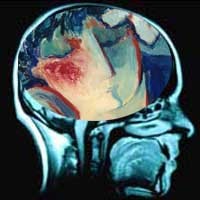

Tidak perlu menjadi Deddy Corbuzier untuk dapat membaca pikiran. Penelitian saat ini menunjukkan akan adanya mesin pembaca pikiran. Menyeramkan atau berguna?